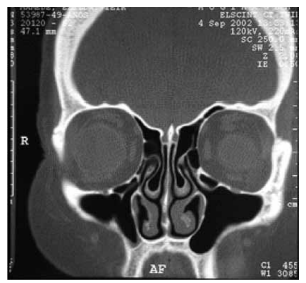

Observe a tomografia computadorizada a seguir.

Qual estrutura pode ser identificada nessa imagem?